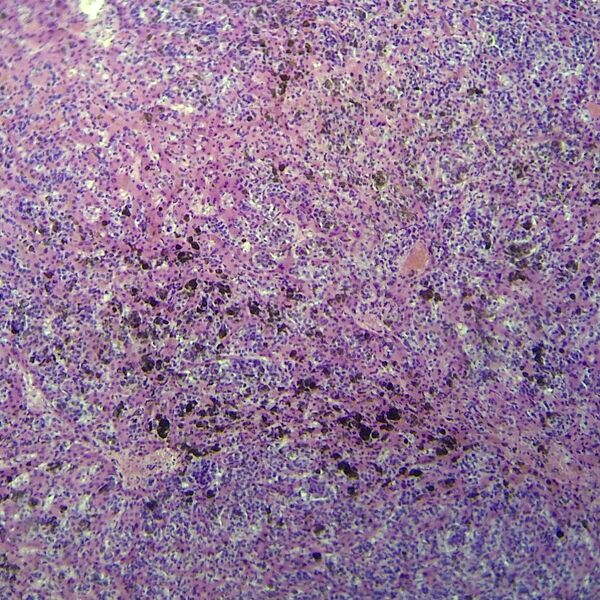

Мелано́ма (лат. melanoma, melanoma malignum ← др.-греч. μέλας «чёрный» + -ομα «опухоль»), уст. меланобласто́ма — злокачественная опухоль, развивающаяся из меланоцитов — пигментных клеток, продуцирующих меланины. Наряду с плоскоклеточным и базальноклеточным раком кожи относится к злокачественным опухолям кожи. Преимущественно локализуется в коже, реже — сетчатке глаза, слизистых оболочках (полость рта, влагалище, прямая кишка). Одна из наиболее опасных злокачественных опухолей человека, часто рецидивирующая и метастазирующая лимфогенным и гематогенным путём почти во все органы. Особенностью является слабая ответная реакция организма или её отсутствие, из-за чего меланома зачастую стремительно прогрессирует.

Метастазы

Опухоль метастазирует лимфогенным и гематогенным путём. Клетки опухоли, распространяясь по лимфатическим сосудам, образуют первые метастазы в регионарных лимфатических узлах. Гематогенным путём (по кровеносным сосудам) происходит метастазирование в печень, лёгкие, кости, головной мозг.